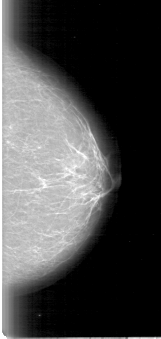

D_4009_1.LEFT_CC

LEFT_CC LINES 5071 PIXELS_PER_LINE 2401 BITS_PER_PIXEL 12 RESOLUTION 43.5 NON_OVERLAY